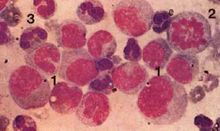

病理檢查2、骨髓像 以異常的顆粒增多的早幼粒細胞增生為主>30%,多數>50%,且細胞形態較一致,原始細胞以下

各階段細胞較少,細胞核形態多不規則有內外漿,外漿中無顆粒,內漿中有大小不均的顆粒根據顆粒的大小可分為:

M3a(粗顆粒型):胞質中充滿粗大的嗜苯胺藍顆粒,且密集融合分布,顆粒也可以復蓋在校上。

M3b(細顆粒型):胞質中嗜苯胺藍顆粒細小,而密集分布。